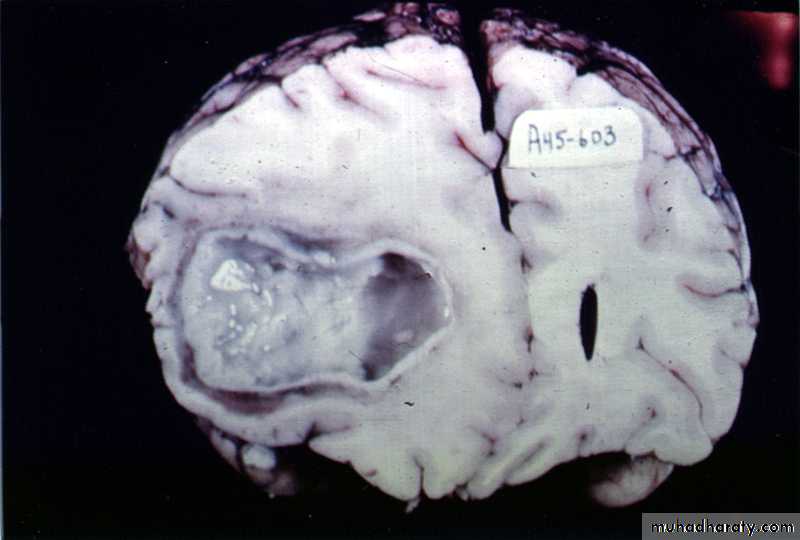

Brain Abscess

Pathology:

The formation of a collagen capsule in a developing abscess is the single most important responsible that limits the spread of infection to the rest of the brain.

Collagen capsule of brain abscess

Neurosurgery